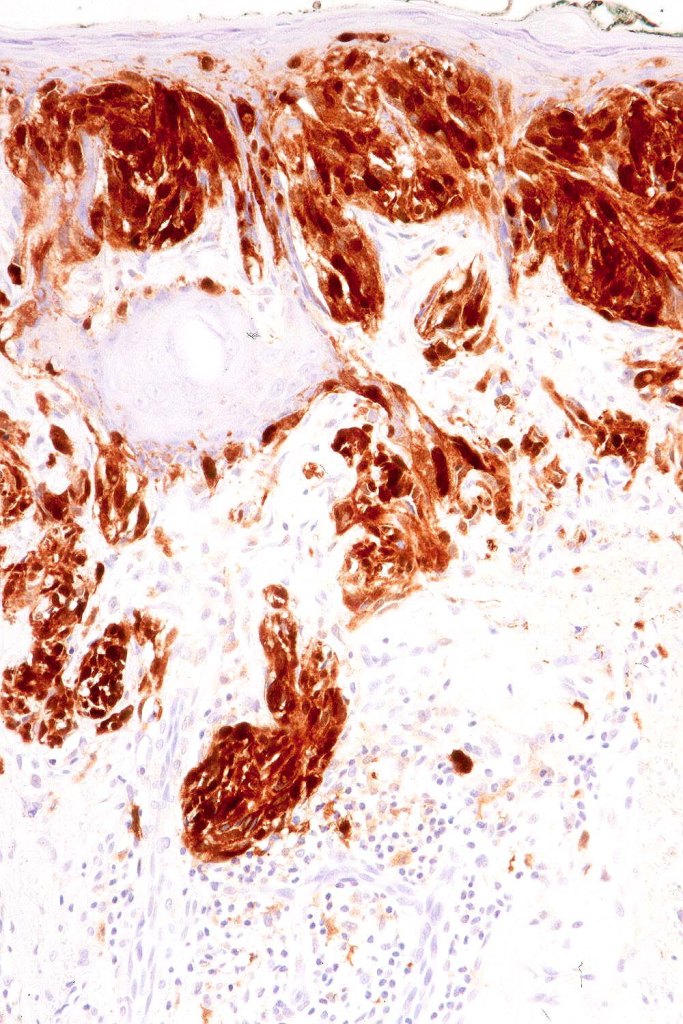

•Invasion can be subtle and may require immunohistochemistry

•Desmoplastic and neurotropic melanoma in a significant number of cases

. SOX10, Melan A, MITF, PRAME, p53+ve